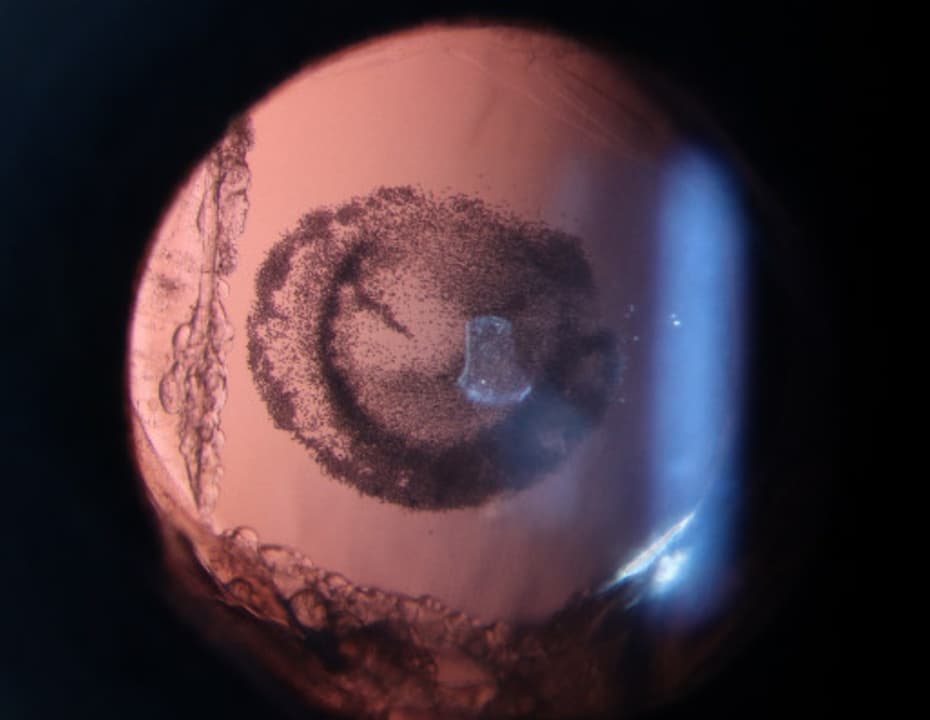

Clinical Images

High-resolution clinical photographs showing various presentations of anisocoria (unequal pupils).